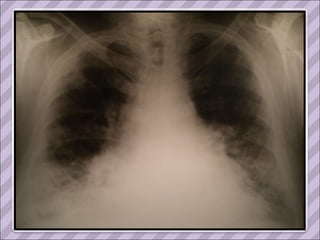

TAC 1993

APP Sarcoidosis torácica  (1993, dx por biopsia ganglionar del mediastino. Estadio II) Compromiso cutáneo (eritema nodoso recurrente y refractario en MMII), ocular (uveítis) y del SNP ( mononeuropatía múltiple). Tratamiento prolongado con corticoides y azatioprina.  Cushing exógeno Diabetes inducida por esteroides Serología positiva para Hepatitis C en 2006